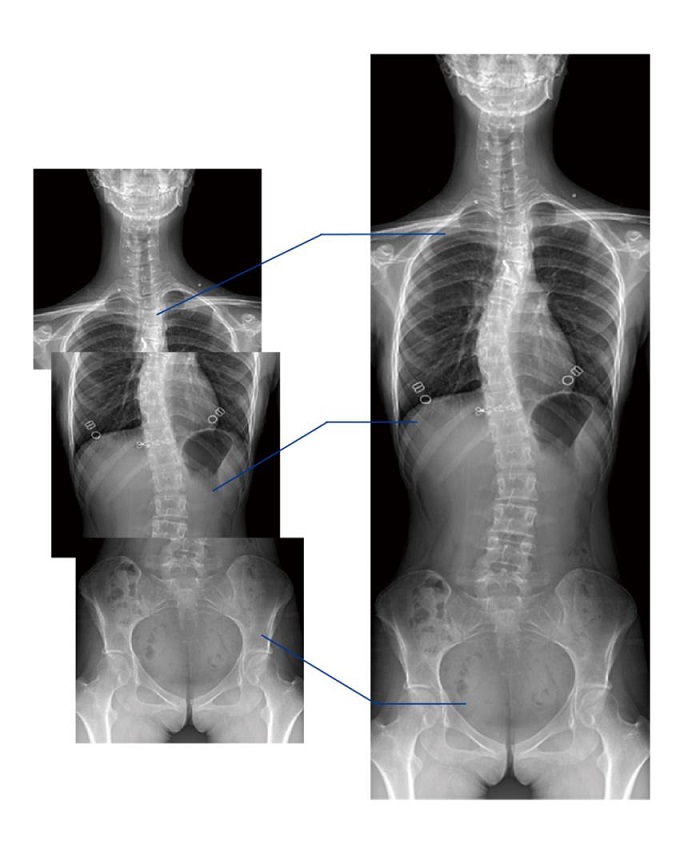

另外,動(dòng)態(tài)DR的全景拼接功能,可通過(guò)對(duì)脊柱、下肢及下肢靜脈造影進(jìn)行分段攝片,然后對(duì)分段圖像進(jìn)行拼接,在一幅X光圖像上完整顯示全脊柱或下肢整體形態(tài)。對(duì)于骨科疾病患者的全脊柱、全下肢病變情況圖像展示更加具有完整性,有助于骨科疾病患者臨床診斷效果的提升。